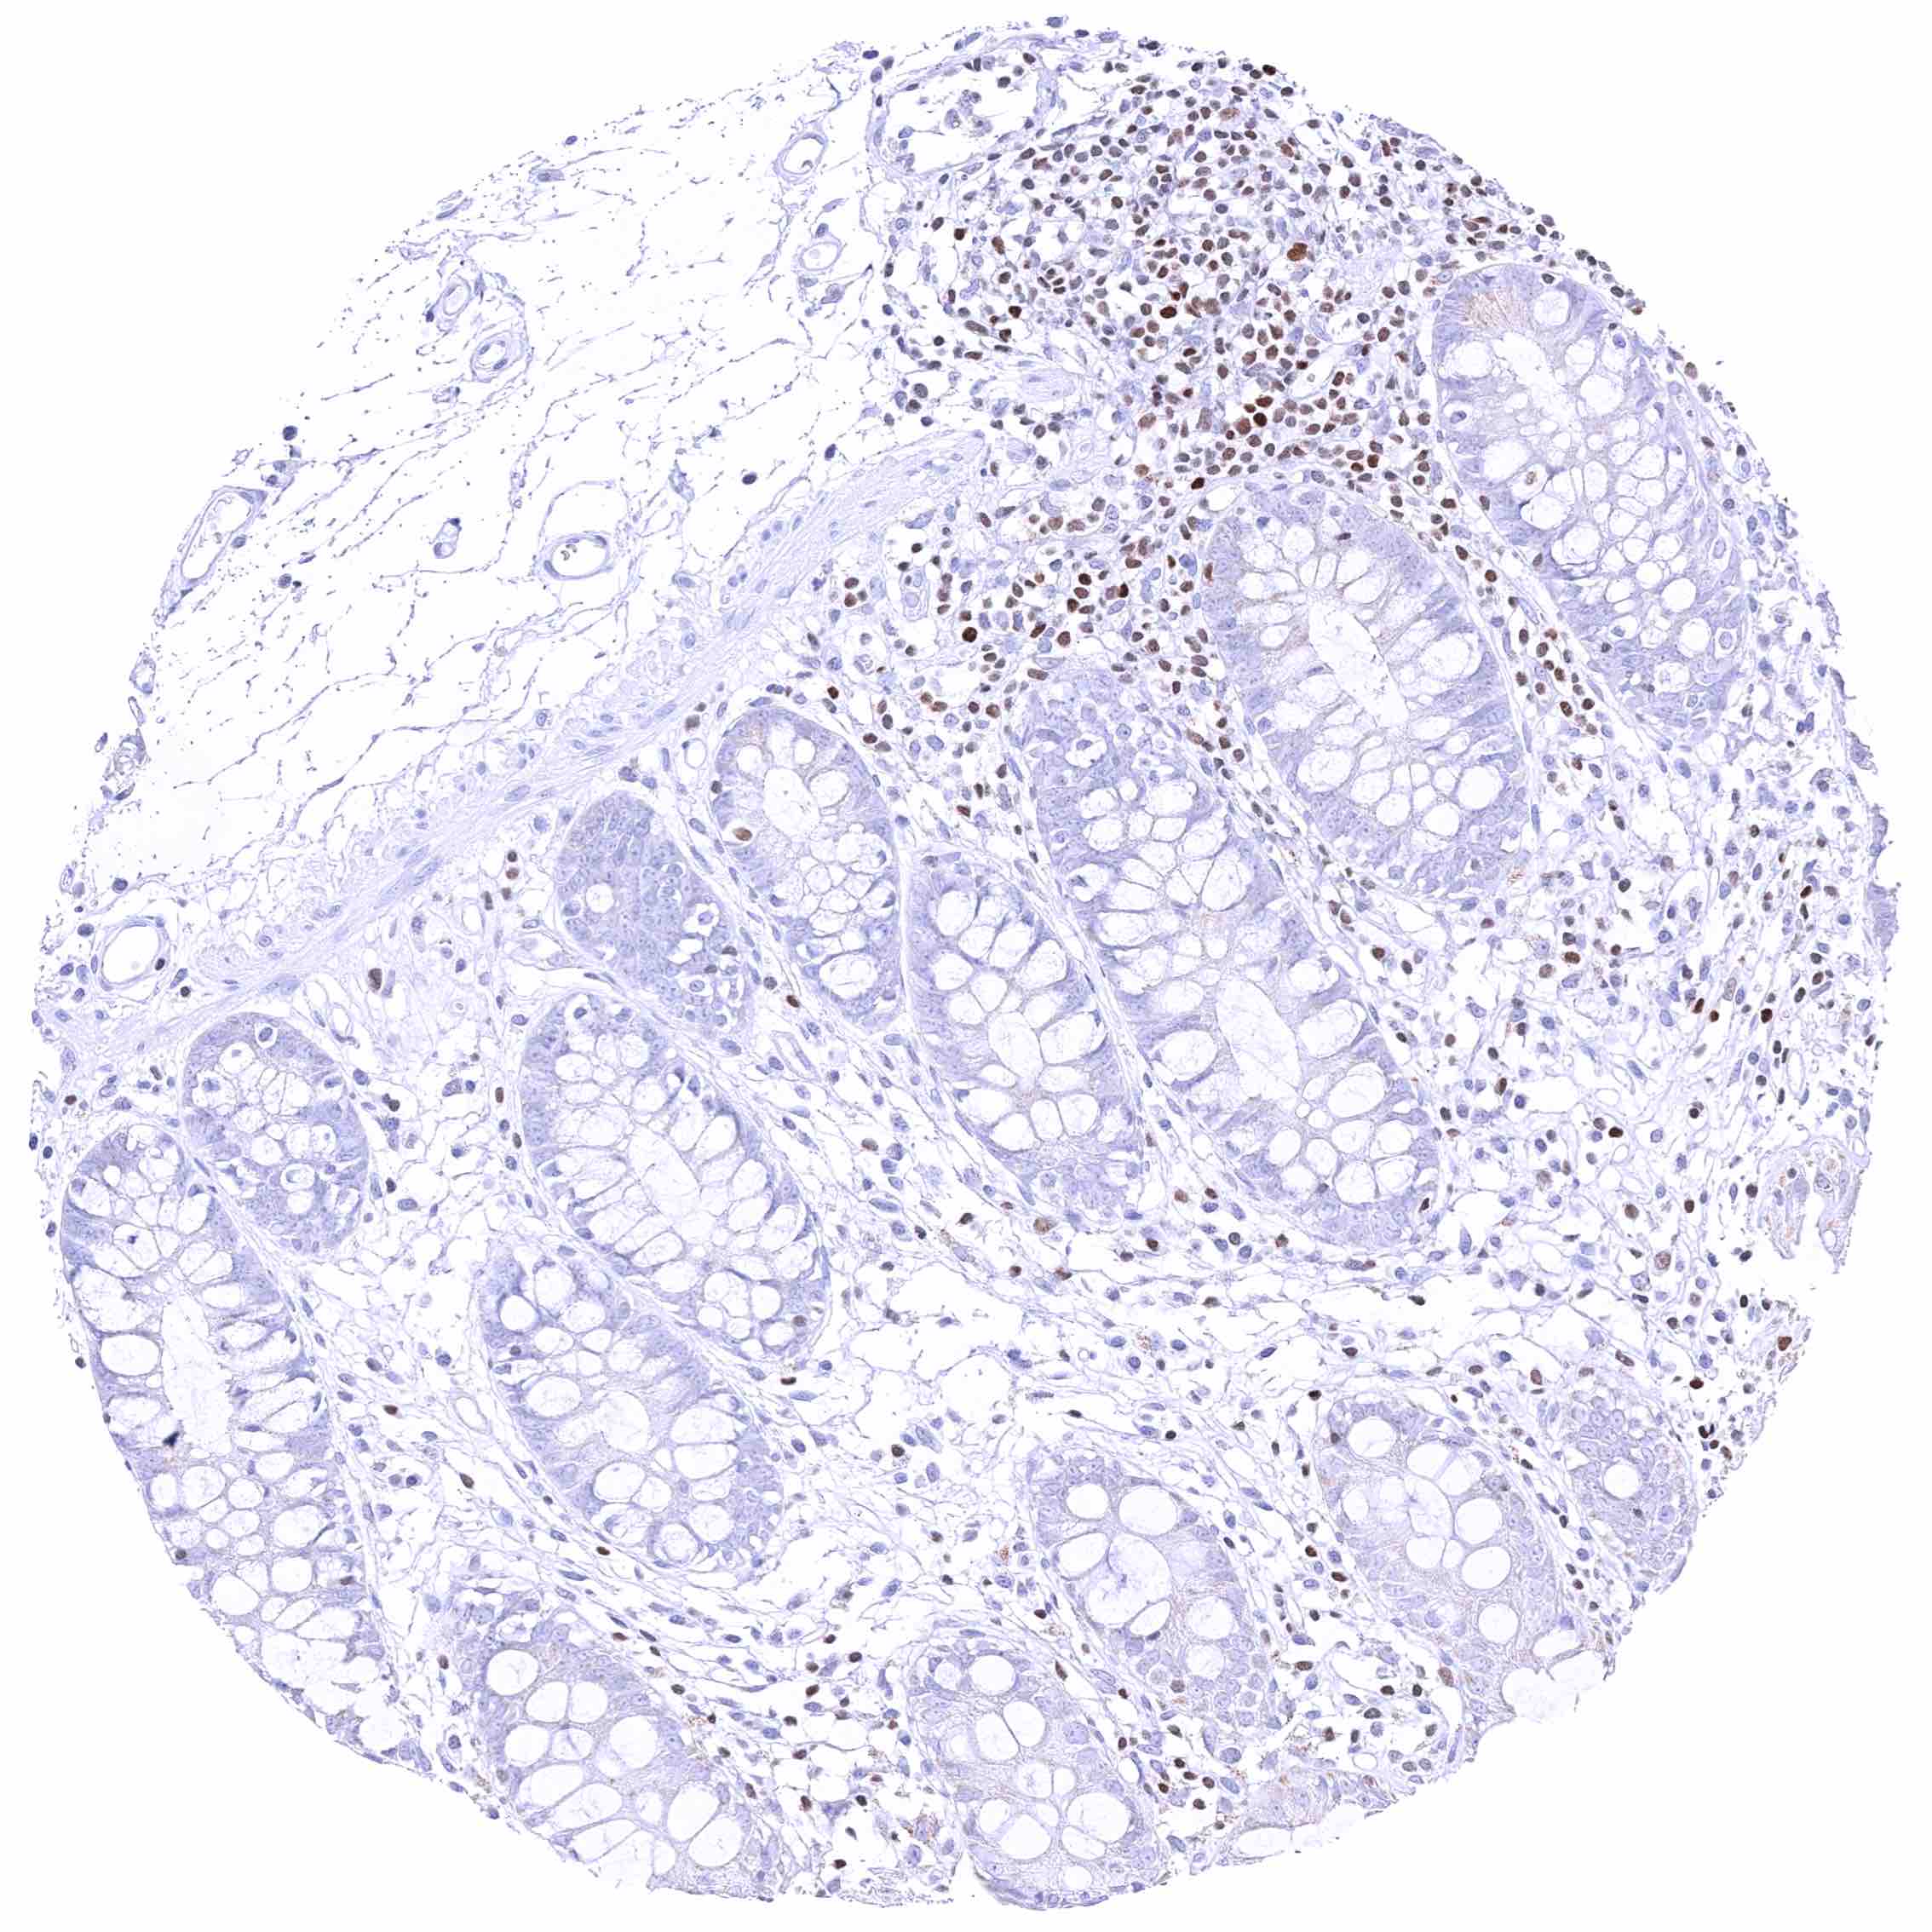

Rectum, mucosa – Nuclear GATA3 positivity of many lymphocytes.

Rectum, mucosa – Nuclear GATA3 positivity of some lymphocytes. Granular cytoplasmic GATA3 staining of epithelial cells.

Colon descendens, mucosa – Nuclear GATA3 positivity of few lymphocytes. Faint cytoplasmic GATA3 positivity of some epithelial cells.